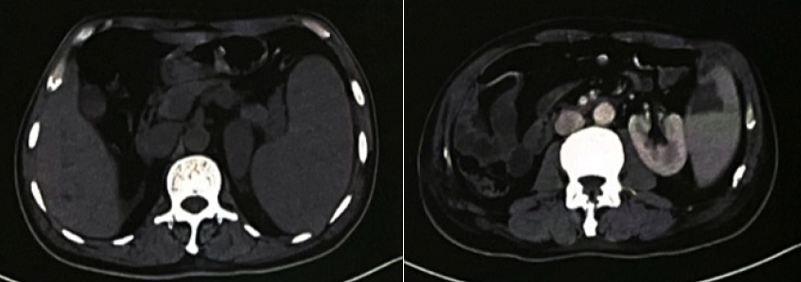

查腹部CT

(图2):脾肿大,局部斑片状低密度影,梗死可能性大;食管胃底静脉曲张(脾静脉明显增宽,胃底部静脉局部增粗扭曲)。

图2 腹部CT